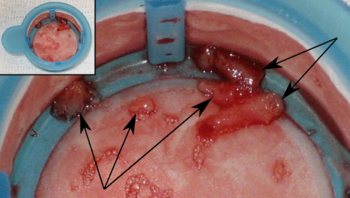

Myocardial rupture

Myocardial rupture is most common three to five days after myocardial infarction, commonly of small degree, but may occur one day to three weeks later. In the modern era of early revascularization and intensive pharmacotherapy as treatment for MI, the incidence of myocardial rupture is about 1% of all MIs. This may occur in the free walls of the ventricles, the septum between them, the papillary muscles, or less commonly the atria. Rupture occurs because of increased pressure against the weakened walls of the heart chambers due to heart muscle that cannot pump blood out effectively. The weakness may also lead to ventricular aneurysm, a localized dilation or ballooning of the heart chamber.

Risk factors for myocardial rupture include completion of infarction (no revascularization performed), female sex, advanced age, and a lack of a previous history of myocardial infarction. In addition, the risk of rupture is higher in individuals who are revascularized with a thrombolytic agent than with PCI. The shear stress between the infarcted segment and the surrounding normal myocardium (which may be hypercontractile in the post-infarction period) makes it a nidus for rupture.

Rupture is usually a catastrophic event that may result a life-threatening process known as cardiac tamponade, in which blood accumulates within the pericardium or heart sac, and compresses the heart to the point where it cannot pump effectively. Rupture of the intraventricular septum (the muscle separating the left and right ventricles) causes a ventricular septal defect with shunting of blood through the defect from the left side of the heart to the right side of the heart, which can lead to right ventricular failure as well as pulmonary overcirculation. Rupture of the papillary muscle may also lead to acute mitral regurgitation and subsequent pulmonary edema and possibly even cardiogenic shock.